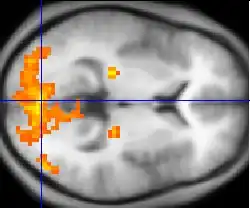

Funktionale Magnetresonanztomografie: Die gelben Bereiche sind die Bereiche mit der größten Aktivität beim Ansehen eines Films

Durch die enormen Fortschritte in den Bildgebungs- und Messverfahren zur Darstellung von Hirnaktivitäten ist es inzwischen auch möglich, die Sprachverarbeitung gesunder Erwachsener ohne medizinische oder ethische Probleme zu beobachten. Ein statisches Abbild des Gehirns liefern die Computertomographie und die Magnetresonanztomografie. Will man jedoch die Abläufe im Gehirn beobachten, kommen dynamische Messverfahren zum Einsatz: Dazu zählen zum einen Messungen der elektrischen Aktivität im Gehirn und dynamische Bildgebungsverfahren.[29]

Neben der Messung und Analyse der elektrischen Gehirnaktivität können bildgebende Verfahren zum Einsatz kommen wie der PET-Scan und die funktionelle Magnetresonanztomografie (fMRT), die Einblicke in das arbeitende Gehirn und damit speziell in die Sprachverarbeitungsprozesse geben.[31]